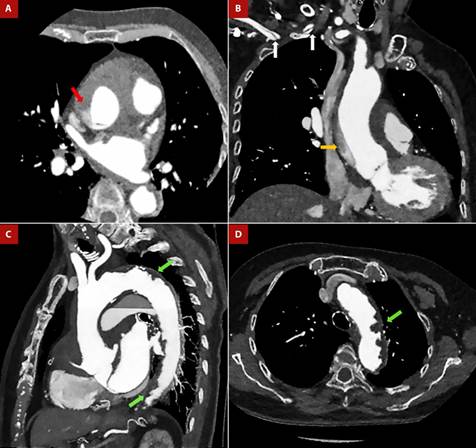

Figure 1 Anterior Q infarction in Shaggy aorta and Stanford “A” aortic dissection. An 80-year-old female patient was admitted to the emergency room with a diagnosis of a 3-day evolving anterior Q infarction. During the attempt to cannulate the left coronary artery, contrast retention was detected in the ascending aorta, so CT angiogram was performed. A, B. Dissection flap is seen at the sinotubular junction (red arrow), with an ascending trajectory to the proximal aortic arch (orange arrow) and extending through the brachiocephalic trunk to the proximal segment of the right subclavian artery (white arrows). C, D. Complicated plaques in the aortic arch and descending aorta (green arrows). Diffuse atheromatosis is observed at the aortic arch, with an image suggestive of an intraluminal thrombus.